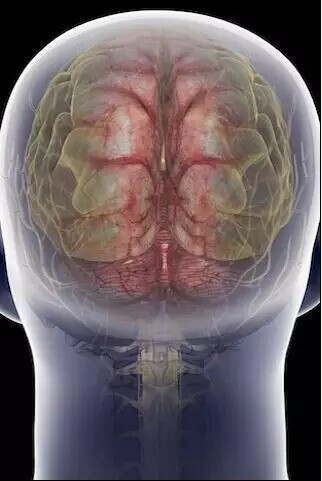

大脑

颈椎、大脑